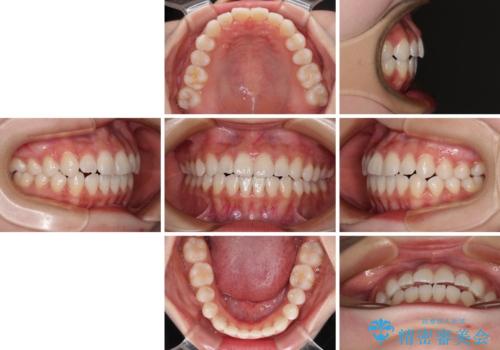

- 前歯のデコボコと非接触の上下前歯を気にして来院された患者様です。

上下前歯の隙間は舌の突出癖によるもので、隙間改善のためには舌のトレーニングがとても重要となります。

口元の突出感はないため、抜歯矯正の適用ではありませんが、デコボコを解消する際に外側に拡大されてしまうと治療前と比べて出っ歯になった印象にもなるため、舌の突出癖の改善が必須となります。

舌のトレーニングは、突出癖がなくなるまで必要であり、矯正治療後に突出癖が残ると、あっという間に隙間が空き、後戻りでデコボコとなってしまいます。